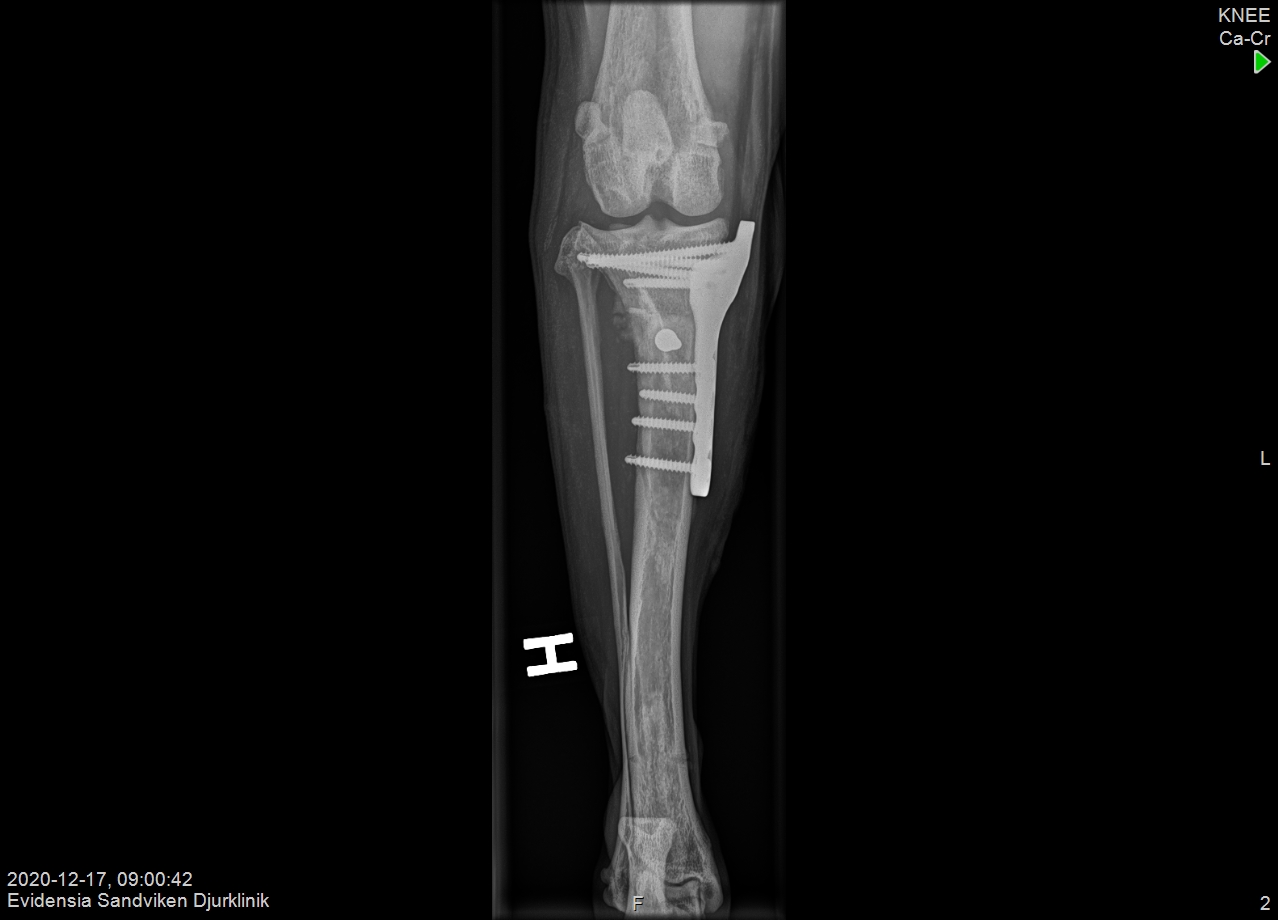

Here is another case from Dr. Hugo Schmökel (DVM, PhD, Dipl. ECVS, MRCVS) of a 5kg dog, featuring the LeiLOX CBLO 2.0mm locking plate.